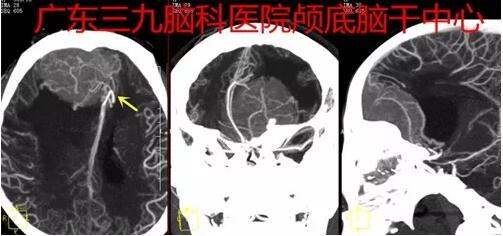

图2:2017-10-31 头颅CTA示病变内示多发异常血管影,血供异常丰富,与双侧大脑前动脉A2段受推压,并关系密切